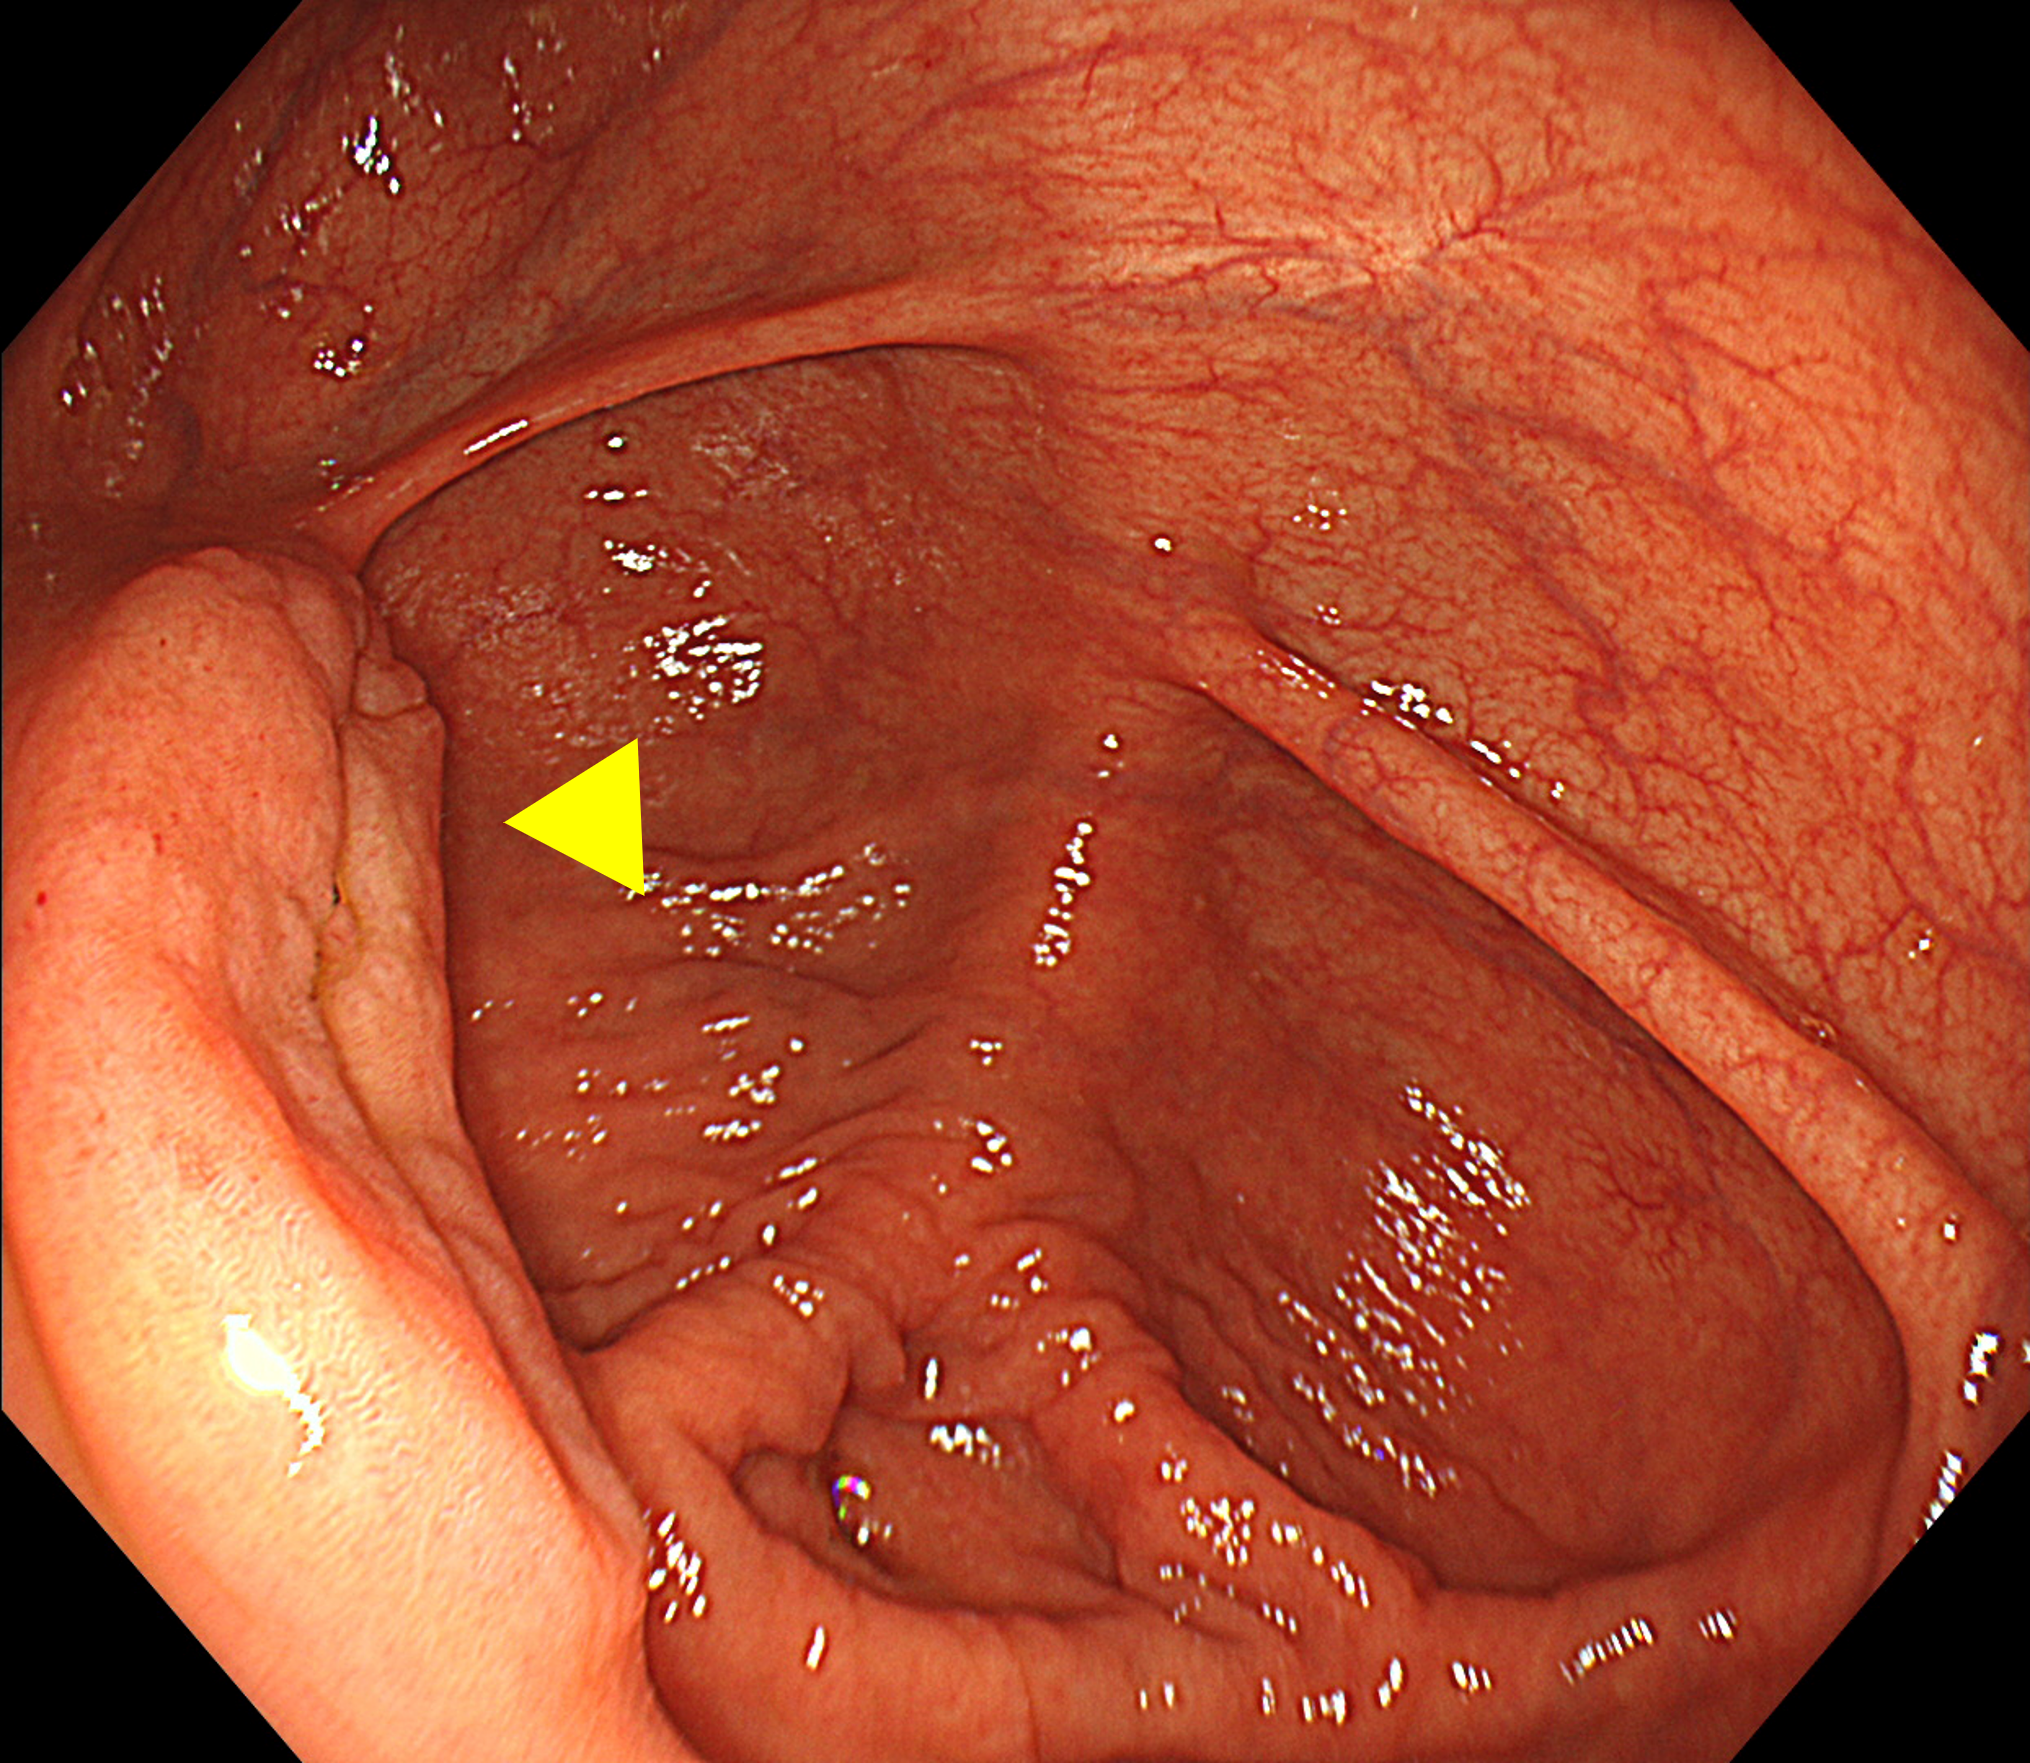

盲腸では、虫垂開口部周囲や回盲弁の裏側が死角となりやすい(※Figure1)。盲腸底部から全体を俯瞰するように観察し、回盲弁は唇裂部を意識して十分に送気・近接観察を行うことが重要である(※Figure2)。

• ※Figure 1. 虫垂口に入り込む病変

• ※Figure 2. 回盲弁下唇裏側にある0-Ⅱa病変

(a) 回盲弁正面視(病変は見えない)

(b) 回盲弁下唇裏側をめくるように観察